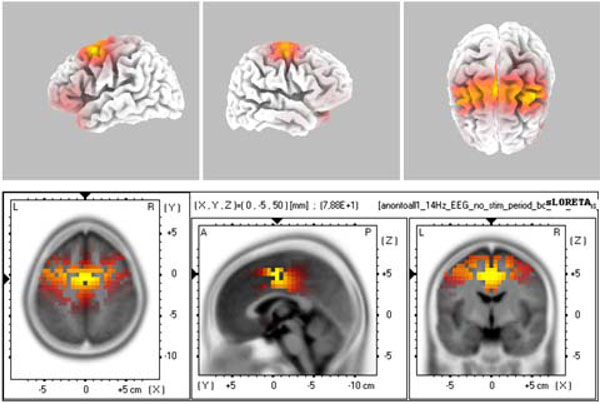

Spontaneous (Unevoked) Spindle Oscillation Activity

The source localization revealed BA6 as the major current density maxima in 6 out of 9 patients. The level of the propofol anesthesia is over the range of 1.2 µg/mL for these data sets (which coincided with the loss of consciousness). The spontaneous activity from every participant of the current study is included in the Appendix. The left column denotes the spectrograms. The sLORETA images and the maxima 3D coordinates as well as the Broadman areas are also provided. The locations from the maximal activity areas include, BA6 (5 subjects), BA9, BA10 (2 subjects), BA21 (2 subjects), BA24 (2 subjects), BA37. A sample is provided in Fig. (4), which presents activity at BA6 for the spindle oscillations during an unevoked condition.

The sLORETA image of maximal evoked activity at BA6. Upper panels indicate 3D representations and lower panel presents the sLORETA images with XYZ coordinates.